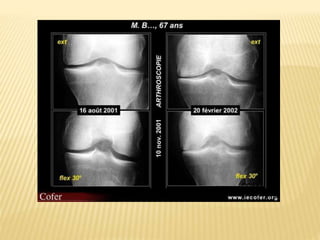

Les signes cardinaux de l’arthrose sont :

• Le pincement localisé de linterligne articulaire

• L’ostéocondensation sous-chondrale.

• Les geodes sous-chondrales.

• L’ostéophyte.